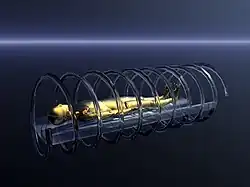

- Elektronenstrahl-Scanner – Diese Geräte der fünften Generation wurden ca. bis zur Jahrtausendwende gebaut. Es bewegen sich hier keine mechanischen Komponenten mehr. Um den Patienten herum befinden sich ein 360°-Kreis mit Detektoren und ein Ring aus einem Material wie zum Beispiel Wolfram, welches als Target (Ziel) für den Elektronenstrahl einer Elektronenkanone dient. Nach dem Prinzip einer Braunschen Röhre wird dieser Elektronenstrahl, mittels elektromagnetischer Felder, jeweils zur gewünschten Position auf dem Targetring gelenkt. Wo er auftrifft, entsteht Röntgenstrahlung, die den Patienten durchleuchtet. Um die vollen 360 Grad des Ringes abdecken zu können, werden mehrere Elektronenkanonen und Ablenkanordnungen verwendet, die in regelmäßigen Abständen um das Target herum angebracht sind. Durch diese Technik konnten extrem schnell Bilder erzeugt werden, sogar Echtzeitaufnahmen vom schlagenden Herzen waren möglich, da sich während der Aufnahme keine mechanischen Teile bewegten, sondern lediglich der Elektronenstrahl um den Patienten geführt werden musste. Dies war im Millisekundenbereich möglich, während die schnellsten CTs selbst heute für eine 360°-Aufnahme noch mehrere Zehntelsekunden benötigen. Diese Geräte haben sich wohl aufgrund des hohen technischen Aufwands und damit des hohen Preises im medizinischen Alltag nicht durchgesetzt, wurden jedoch aufgrund ihrer hohen zeitlichen Auflösung von bis zu 30 ms in der Kardiologie sehr lange verwendet.[11] CT-Aufnahmen des Herzens hoher Qualität können heute mit hochzeiligen Spiral-CTs (64–640 Zeilen) in vergleichbarer bzw. besserer Qualität bei weit geringeren Kosten erstellt werden.